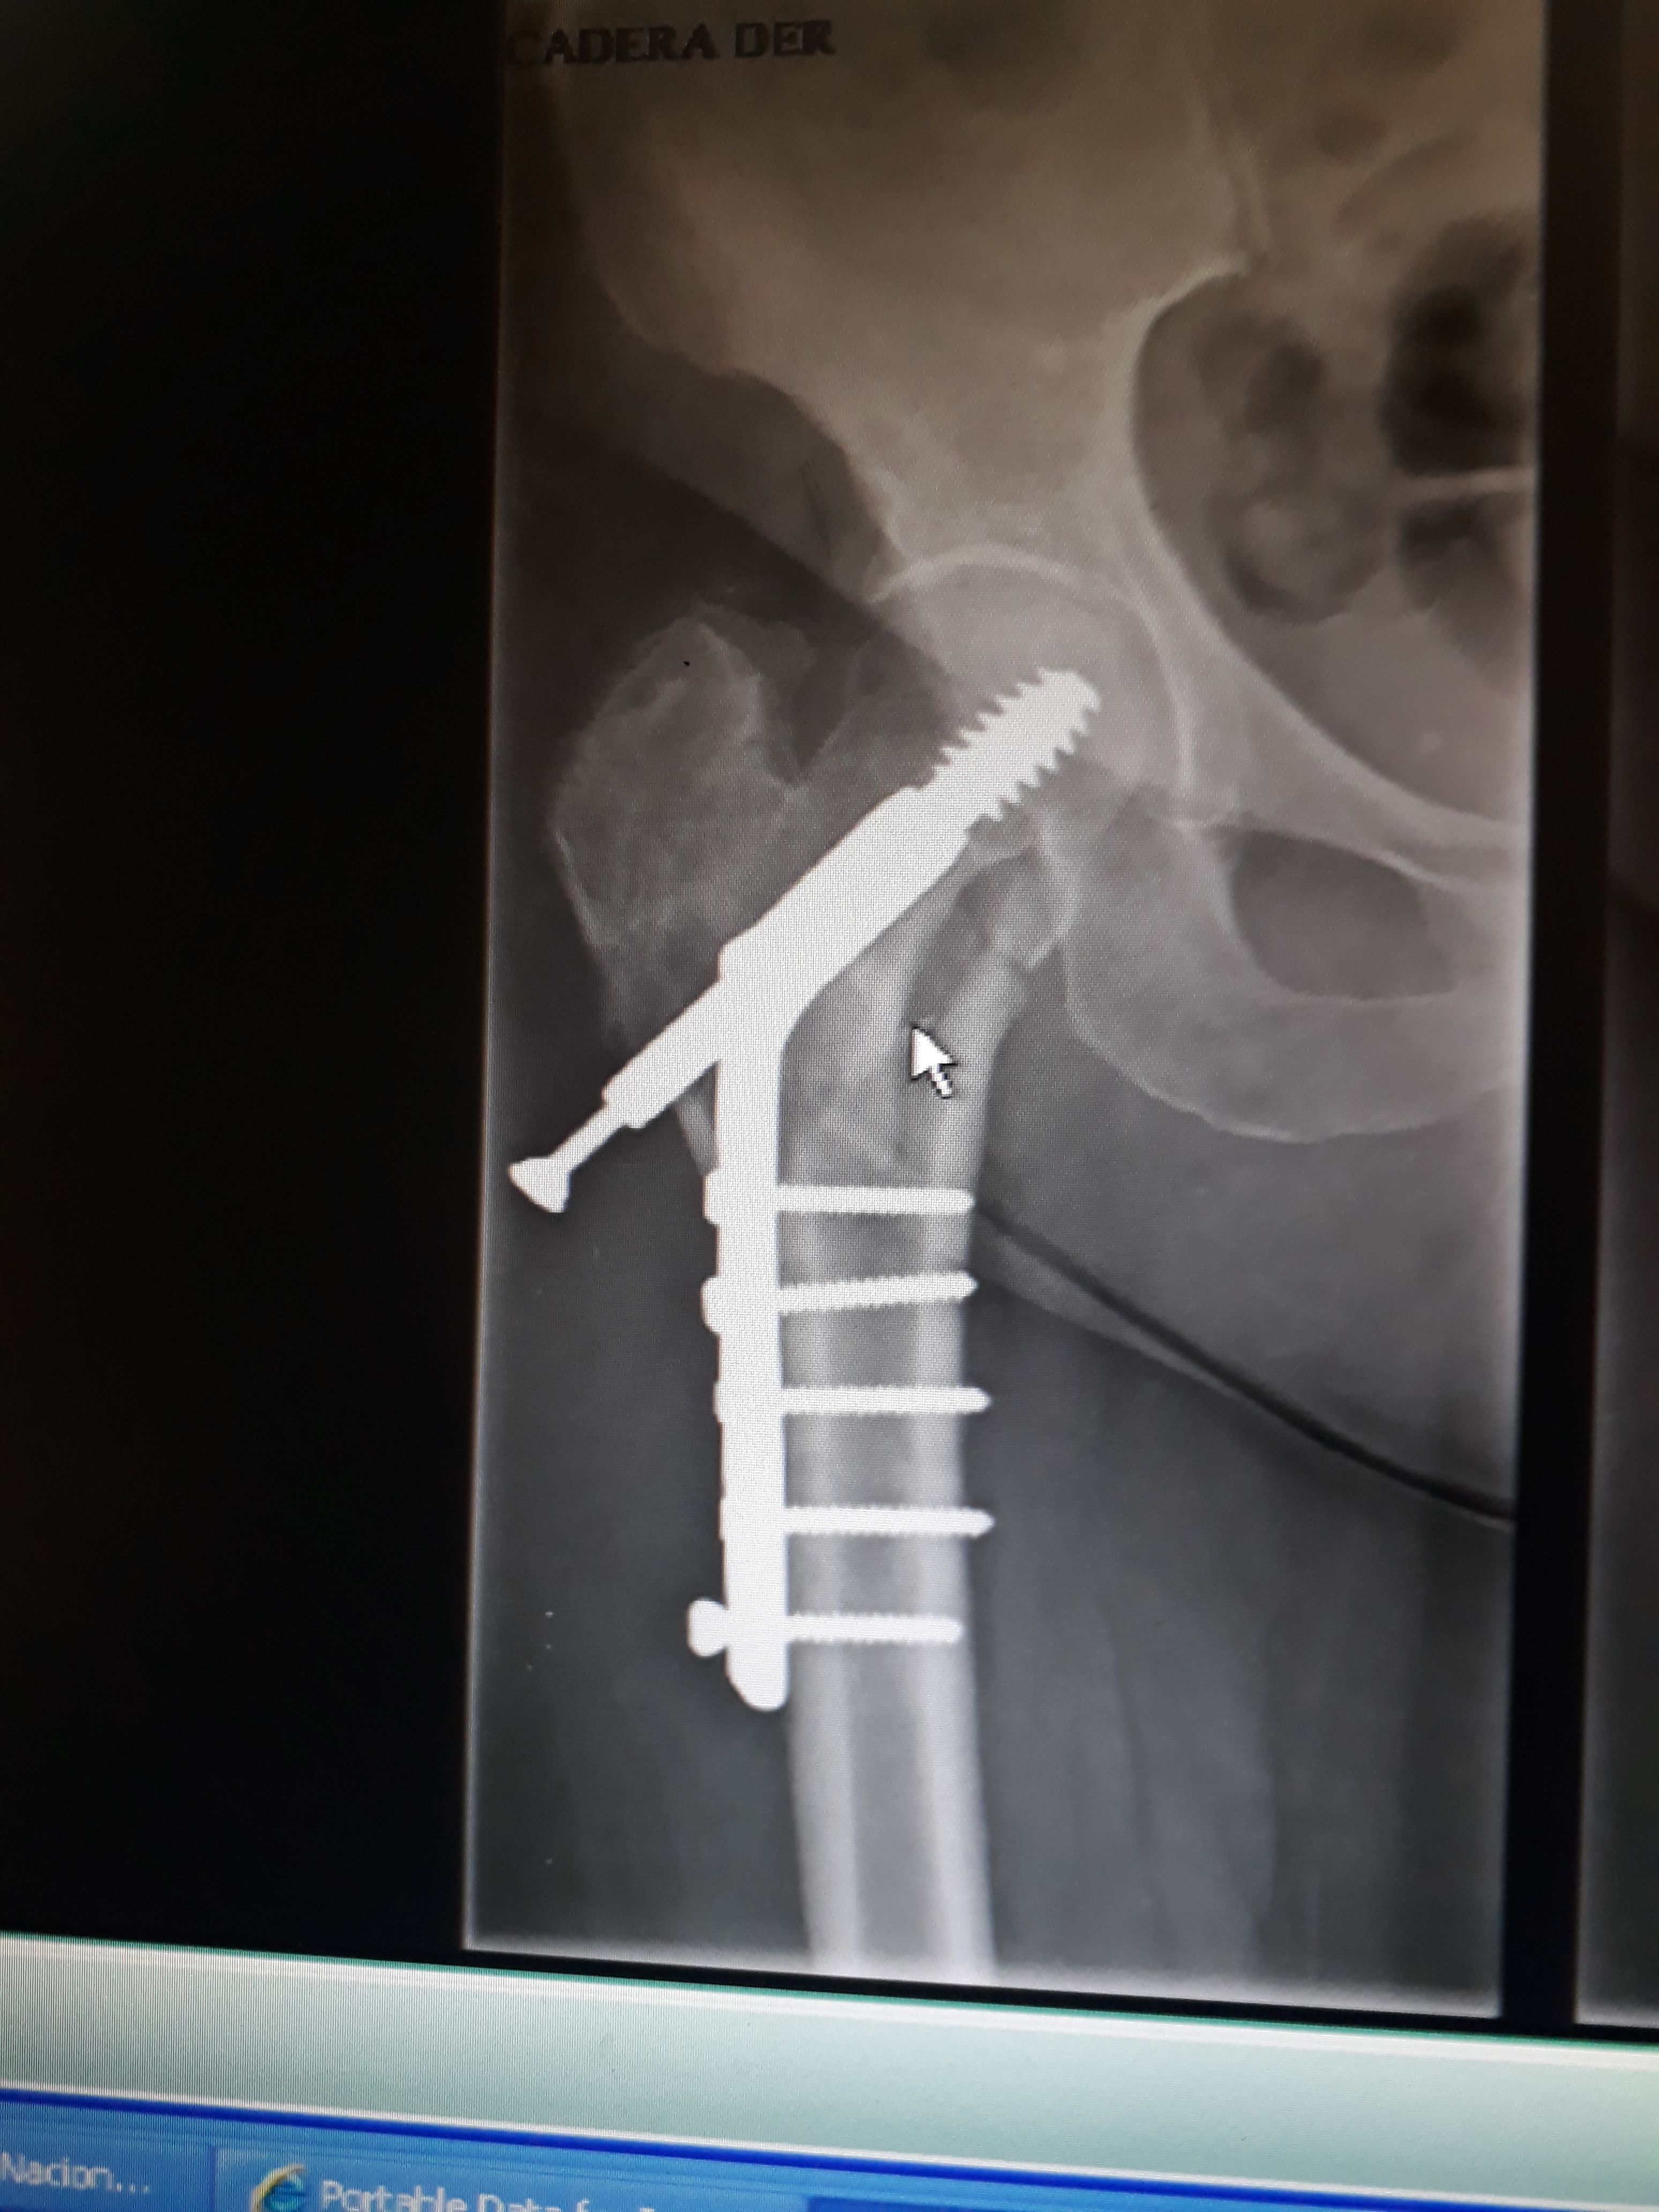

SURGERY OF A FEMUR (TECHNIQUE OR SYSTEM FAILURE)

A 58 years female, with a subthrochanteric fracture treated with a DHS system  female, with a subthrochanteric fracture One month after the surgery, without weight support   Surgical technique or DHS system Failure?